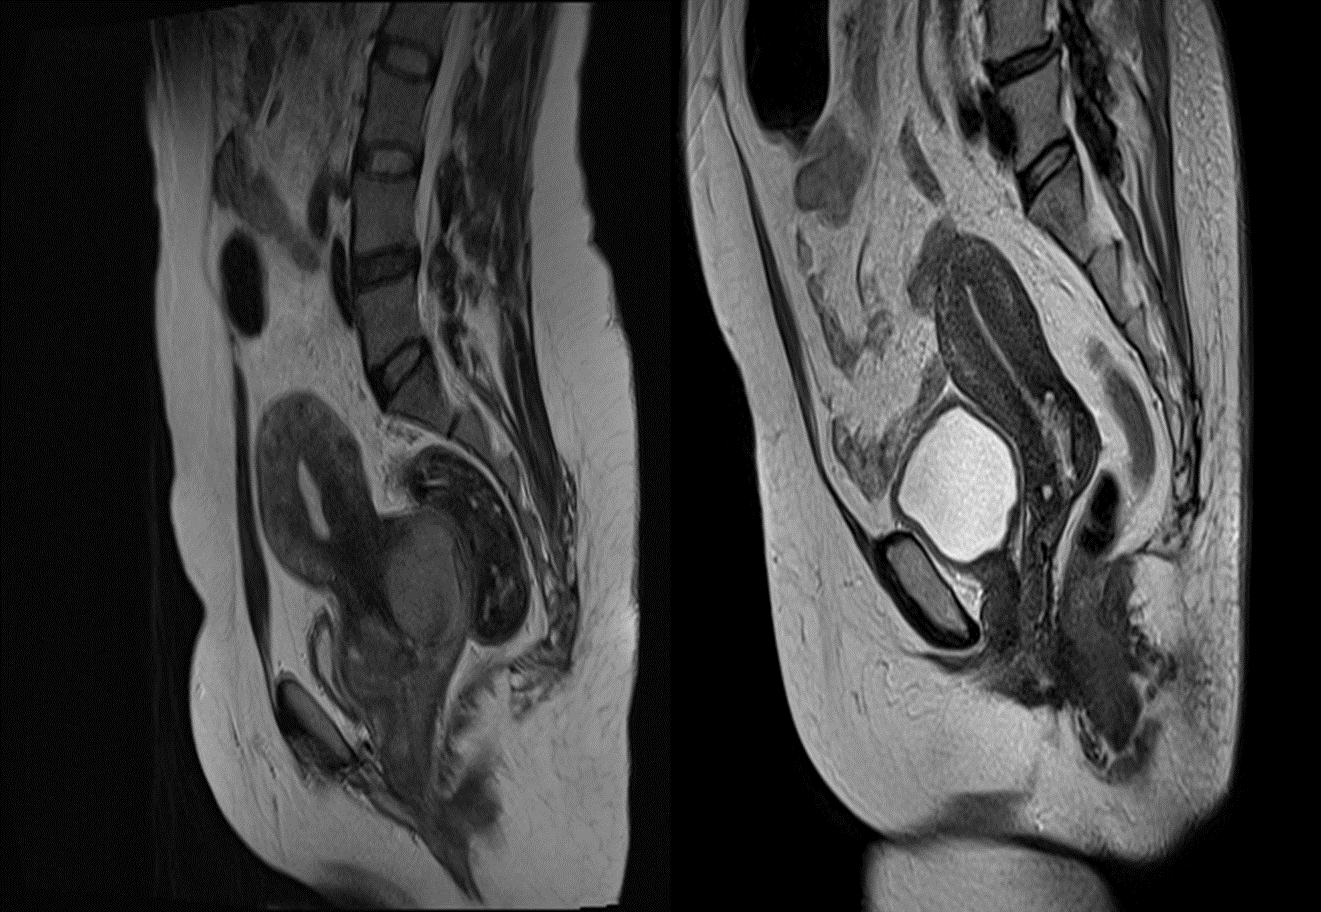

• MRI is very accurate in assessing the local extent of the tumour. (a)Sagittal T2-weighted MRI scan showing a tumour confined to the cervix.

(b) Sagittal T2-weighted MRI demonstrating a polypoid tumour mass distending the endometrial cavity